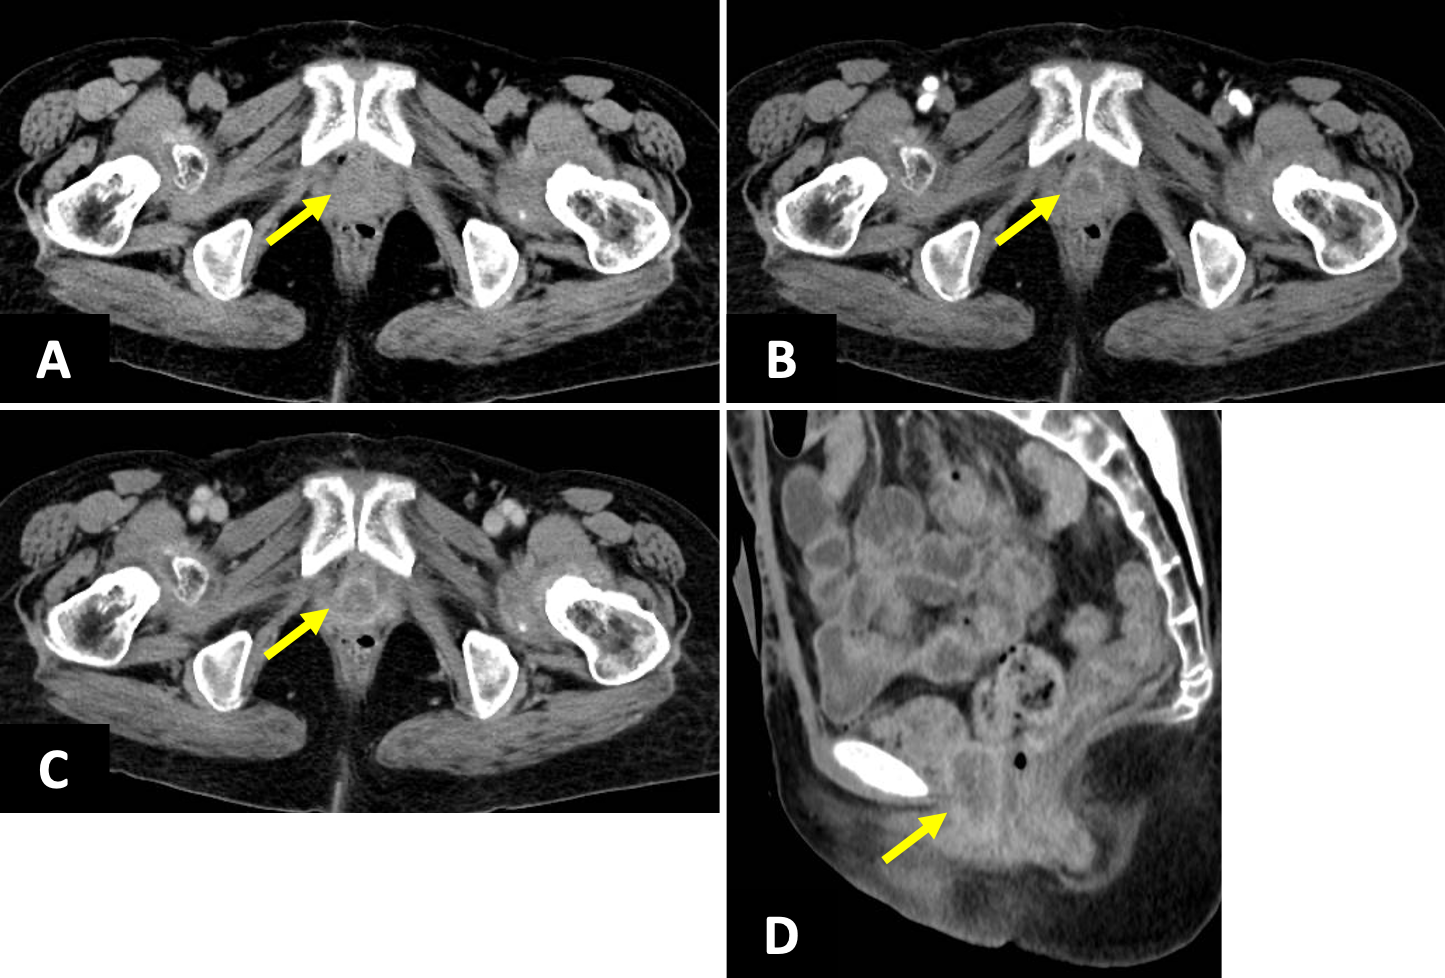

膀胱上皮内癌に対し膀胱全摘+回腸導管造設後。術後2年目に残存尿道から出血が出現したため造影CTを施行。尿道再発を疑う所見を認め、さらなる精査目的でガドビスト造影MRIを施行した。

症例解説

臨床および画像所見から、膀胱癌の尿道再発の術前診断のもと腫瘍切除が施行された。病理診断では、神経内分泌分化を伴う尿路上皮癌との結果であり、膀胱癌再発として矛盾しなかった。

本例では残存尿道に比較的粗大な腫瘤が形成されていたものの、CTでは若干所見が不明瞭であった。しかし、MRIを追加で撮像したことで病変を容易に検出することができた。骨盤内には複数の臓器が隣接して存在しているため、MRIの高いコントラスト分解能が診断に有用であった。なお、当施設には尿道専用のプロトコルが無かったため、今回の症例では前立腺のプロトコルを転用して撮像している。